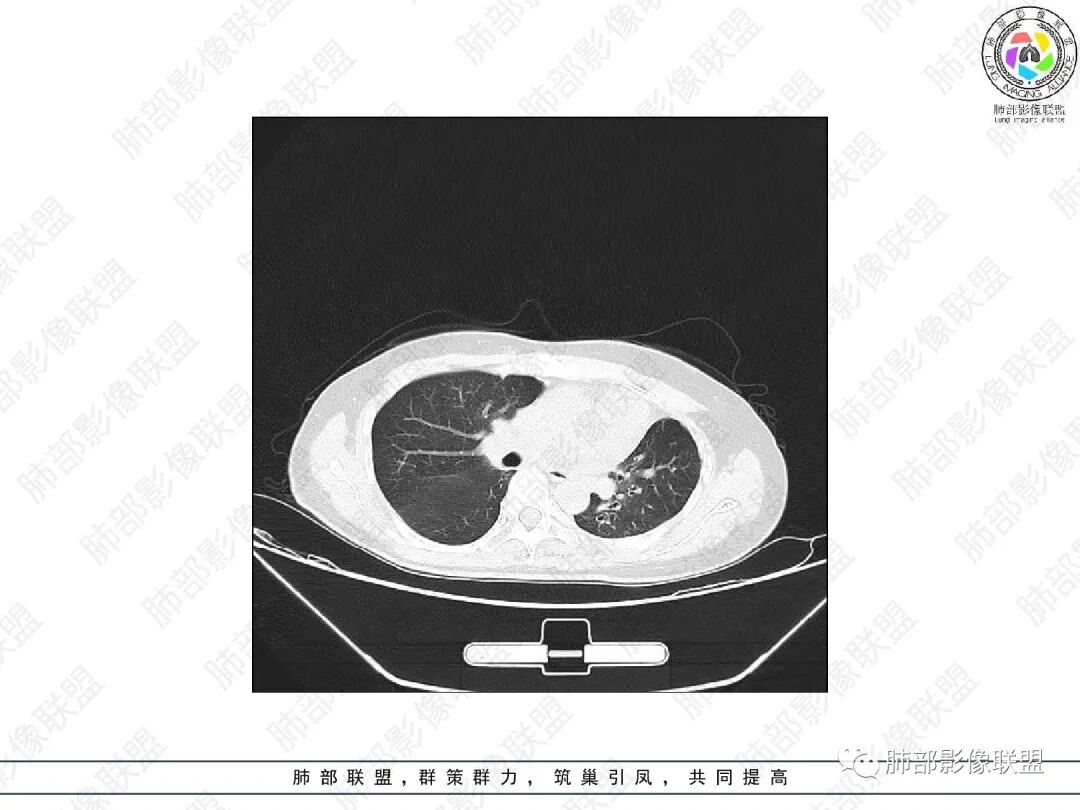

1.中年女性,主因“咳嗽、咳痰半年余”入院,既往史:8年前因左肺病在外院变行左肺叶切除术,诉术后抗结核治疗1年,具体病理等不详。实验室IGE显著增高。

2.胸部CT:右肺上叶及中叶不规则块状影,沿支气管走行方向指套样影,支气阻塞湖嵌塞,腔内可见高密度影。灶周可见磨玻璃,外围见结节影及树芽征。左肺体积缩小,见不规则条索影、胸膜增厚,纵隔牵拉左移。

3.综合分析:结合患者病史及胸部CT主要鉴别ABPA(右肺上叶不规则块影,指套样顺延支气管方向,抗结核治疗1年,肺部病灶仍明显)及继发性肺结核TB(右肺上叶不规则肿块,其可见高密影,边缘模糊,周围卫星灶、树芽征,沿支气管爬行)。

完善气管镜及病理、检验结果(IgE显著增高)等支持ABPA诊断。且给予激素及伊曲康唑治疗后复查胸部CT提示病灶较前吸收,所以诊断明确。